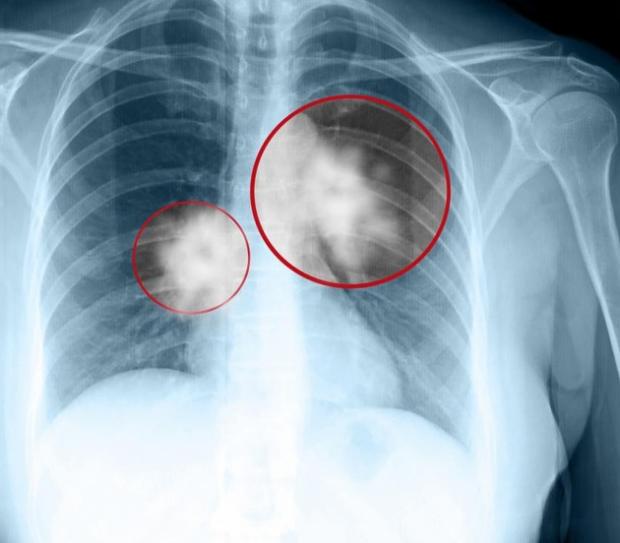

Cuba đã phát triển thành công và sở hữu một loại vắc-xin chống ung thư phổi. Mang cái tên Cimavax, nó có thể biến ung thư phổi giai đoạn cuối thành một bệnh mãn tính có thể kiểm soát.

Cho tới năm 2011, Bộ Y tế Cuba đồng ý cho phép sử dụng Cimavax trên người. Những bệnh nhân được điều trị miễn phí, trong khi mỗi liều Cimavax chỉ tiêu tốn của chính phủ 1 USD. Đó là kết quả sau một thử nghiệm giai đoạn 2 năm 2008. Các bệnh nhân ung thư phổi được điều trị với vắc-xin đã sống trung bình lâu hơn 4-6 tháng bệnh nhân bình thường. Khi đó, cả Nhật Bản và Châu Âu bắt đầu chú ý đến tiềm năng của công nghệ Cimavax.

Về bản chất, Cimavax không phải là một loại thuốc chống ung thư trước khi nó diễn ra, như mọi người thường định nghĩa về vắc-xin. Trên thực tế, vắc-xin là một chất kích thích hệ miễn dịch. Bởi vậy, Cimavax cũng không giống với các loại thuốc điều trị bình thường, chúng không tấn công trực tiếp các khối u.

Thay vào đó, Cimavax thúc đẩy cơ thể người bệnh sản xuất kháng thể chống lại một hooc-môn tăng trưởng biểu bì. Loại hooc-môn này thúc đẩy sự tăng trưởng tế bào, nhưng mặt khác khiến khối u lớn lên và mất kiểm soát. Kiểm soát được loại hooc-môn này, Cimavax có thể ức chế sự phát triển của ung thư phổi, hạn chế sự di căn của nó và biến ung thư chỉ còn là một bệnh mãn tính để điều trị.

Loại vắc-xin này và cách nó làm việc thu hút được sự chú ý rất lớn của các nhà nghiên cứu Mỹ và Châu Âu. Yếu tố tăng trưởng biểu bì đóng vai trò quan trọng, không chỉ với ung thư phổi mà còn ung thư vú, tiền liệt tuyến, ruột kết, tuyến tụy. Kelvin Lee, một nhà nghiên cứu đến từ Viện Roswell Park cho biết 'Tất cả những bệnh ung thư này là mục tiêu tiềm năng của loại vắc-xin này'. Có vẻ vì vấn đề tài chính eo hẹp, Cuba đã không thể thử nghiệm nó trên các bệnh ung thư khác, ngoài ung thư phổi đến từ những điếu xì gà mỗi ngày.